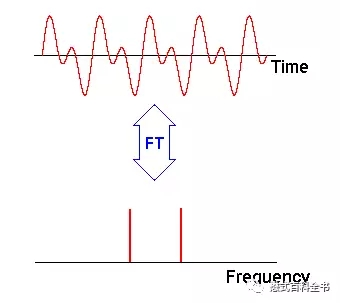

图2:图解傅里叶变换FT,上面为一个时间域函数,随时时间变化,信号的变化函数;下图为一个频率域函数,表示经过傅里叶变换后,该信号的频率。本例中可以看到,上面的信号随着时间变化呈周期性变化,信号形状不是标准的正弦曲线和余弦曲线,说明信号包含两种以上不同频率,经过FT后,把信号的频率分解出来。

傅里叶变换FT:将时间域函数转换为频率域函数;

反傅里叶变换IFT:(反过来)将频率域函数转换为时间域函数。